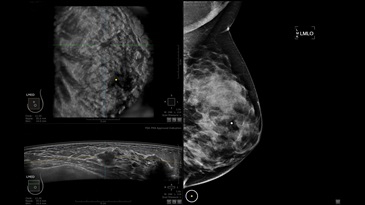

GE INVENIA ABUS – это современный УЗИ аппарат, который создан для точной и эффективной диагностики сканирования с высокой плотностью молочных желез. Выявляемость патологий раковых и предраковых стадий заболевания составляет 55%, что в конечном счете позволяет ставить врачу точные и своевременные диагнозы. Традиционные методы использования маммографии не показывают такой выявляемости, ограничиваясь лишь 3-38%.

УЗИ-аппарат GE INVENIA ABUS позволяет проводить максимально операторонезависимые процедуры, что значительно снижает риск неправильной постановки диагноза и сопутствующие издержки на обработку информации. Система готовит отчет в течение 3-х минут после сканирования, это безусловное преимущество по сравнению с обычным УЗИ сканером.

• Получение объемных 3D изображений с возможностью покадрового просмотра

• Получение изображений в поперечной плоскости (в реальном времени) и в коронарной плоскости (статическая, для указания нахождения соска)

• Отображение объемных 3D ультразвуковых изображений, которые состоят из традиционных поперечных и воссозданных коронарных и сагиттальных проекций

• Стандартизованная ориентация изображения: «толстый срез» в коронарной плоскости; поперечная; сагиттальная плоскость; радиальный и антирадиальный поворот изображения; просмотр исключительно области интереса